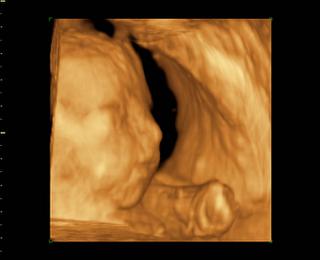

@lucy56 morfoligicky utz je zameraný na hodnotenie správnosti vývoja jednotlivých orgánov plodu a zároveň sa odmeraním určitých parametrov hodnotí aj správnosť rastu dieťaťa. nebudes tak dobre vidiet dietatko ako na 3D. 3D utz :Moderný 3D ultrazvuk umožňuje vidieť pohyby Vášho bábätka, ako na filmovom plátne. Pohľad do tváre pôsobí na budúcu mamičku ukľudňujúco. Prepočítajme spolu prstíky a presvedčme sa, že je všetko v poriadku.Celé vyšetrenie je možné uchovávať na DVD nosiči.Najvhodnejší je záznam v 22-26. týždni tehotenstva.